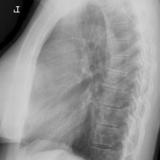

Thymic carcinoma Lat

Date: 08/15/2012

Views: 10195